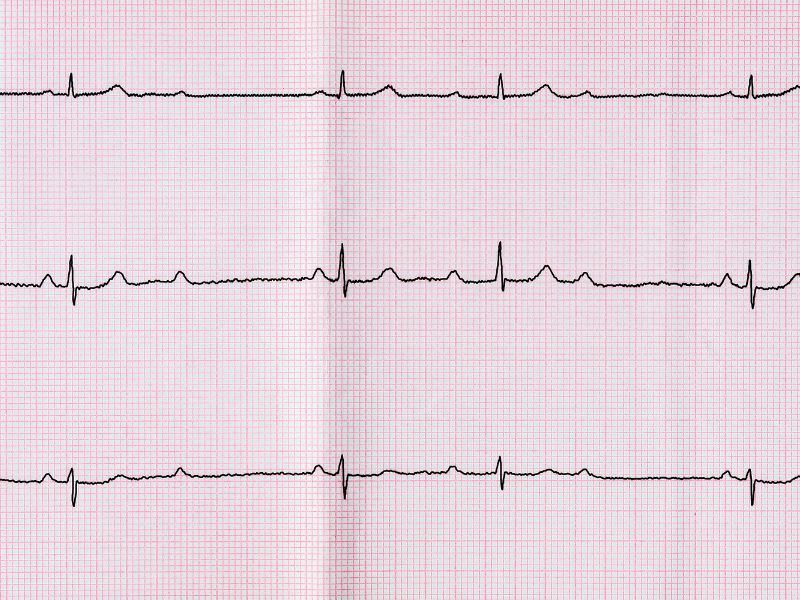

Figura 3: A avaliação do átrio ocorre principalmente observando a onda P nas derivações DII e V1.

Figura 3: A avaliação do átrio ocorre principalmente observando a onda P nas derivações DII e V1.

Figura 2: Ritmo sinusal alternando com ritmo de fibrilação atrial. A análise do ritmo é a segunda etapa na interpretação dos achados do traçado. Figura 3: A avaliação do átrio ocorre principalmente observando a onda P nas derivações DII e V1.

Figura 3: A avaliação do átrio ocorre principalmente observando a onda P nas derivações DII e V1. Figura 4: Exemplo de bloqueio atrioventricular de segundo grau Mobitz I (Fenômeno de Wenckebach). Observe o aumento progressivo do intervalo PR.